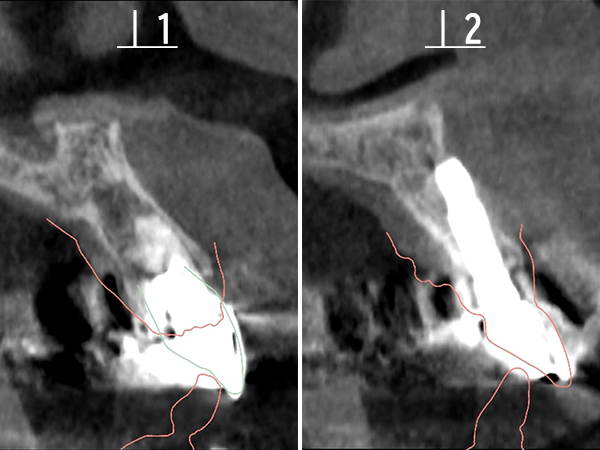

CTによる診査

CTを撮影し、歯根の長さや根尖病変の大きさを精査しました。

CTによるシミュレーション

2|

|1